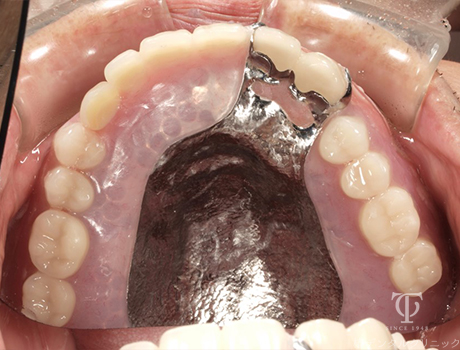

Case03

術後の上顎内冠

-

術後の下顎内冠

AGCテレスコープ義歯装着

- 症状

- 右上の痛み

- 治療期間

- 約1年半

- 治療費用

- (上顎)AGCテレスコープ義歯:1,500,000円

(下顎)AGCテレスコープ義歯:1,500,000円

右上の歯が痛いということで来院されました。AGCテレスコープという方法でかみ合わせを再構築しました

【リスク・副作用】

入れ歯を清潔に保たないと虫歯や歯肉炎、歯周病になるリスクがあります。